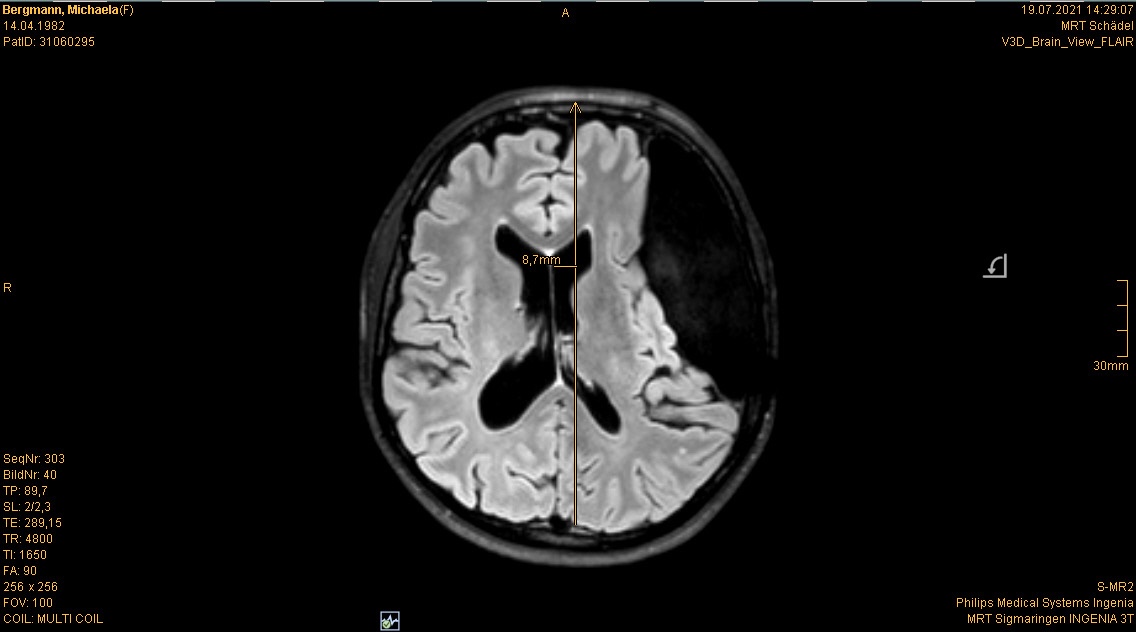

Im Juli stand ja auch noch mein jährliches Kopf MRT an. Ist ja schon quasi „same procedure as every year“. Es gab nichts überraschend Neues oder so. Wenn man es optimistisch sieht kann man sagen: Unverändert. Wenn man es realistisch sieht: gleich beschissen wie vorher

Für alle, die sich neu hier auf meinem Blog tummeln und schon an der ein oder anderen Stelle von meinem „Untermieter“ gelesen haben, sei er hier noch einmal mit den aktuellsten Bildern „vorgestellt“

Die Bilder sind also die aktuellsten vom 19.07.2021. Ja ich weiß, der ist ja riesig, ja ich weiß, dass das ja echt shit ist usw. usw. Aber das weiß ich nun schon seit dreizehn Jahren und ich habe mich damit arrangiert und abgefunden. Womit wir zum nächsten Gedankenthema kommen.

Es ist für mich ja nicht mehr schockierend, wenn ich die Bilder sehen, denn ich weiß ja was mich erwartet. Aber für den ein oder anderen Außenstehenden oder mich noch nicht kennenden Mitarbeiter in der Radiologie im Krankenhaus ist das doch schon immer wieder was Besonderes. Und als ich dieses Mal so den MRT Gang entlang schritt und herein gerufen wurde, wusste die eine Mitarbeiterin, dass ich nun schon zum 37sten Mal das ganze Prozedere über mich ergehen lasse und sagte dementsprechend nicht mehr viel zu mir (bzgl. alles mit Metall muss ausgezogen werden vorher, dann wird der Kopf mit einer Art Kopfkäfig fixiert, dass man ihn während der Aufnahmen nicht bewegt usw.). Es läuft alles wie eine Art Routine und im stillen Einvernehmen zwischen uns ab. Der andere Mitarbeiter der da war, war sichtlich irritiert. Und wollte mir zuvorkommen und mich aufklären, wusste aber auch nicht ob er das, weil seine Kollegin (wohl auch seine Vorgesetzte) schwieg, irgendwie nicht richtig wäre usw. Während ich dann immer so im MRT liege und die Bilder gemacht werden (das dauert dann immer gut so zwanzig Minuten) gehen mir auch meist zig Sachen durch den Kopf. Ehrlich gesagt keinerlei Gedanken bzgl. des MRTs selbst, sondern eher bzgl. dem was seit meinem letzten Besuch hier mal wieder alles so los war und passierte.